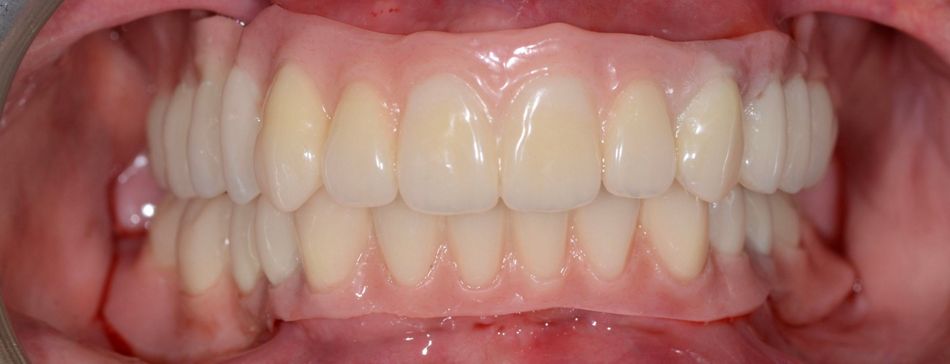

Final rehabilitation of the upper and lower jaws (Figs. 66,67).

The patient’s smile after final prosthetic rehabilitation (Fig. 69).

The patient’s appearance was noticeably improved, and she was very pleased with the result. She appeared cheerful and satisfied, clearly happy with how everything turned out (Fig. 70).

The case was planned and carried out using a fully digital workflow, achieving precise implant placement and prosthetic alignment. The Novaloc® system helped reduce invasiveness by allowing implants to be placed in the existing bone while adjusting the prosthetic axes for the removable prosthesis. The patient was very happy with the result, noticing a significant improvement in both appearance and function, and was impressed by how the digital approach enhanced her smile.